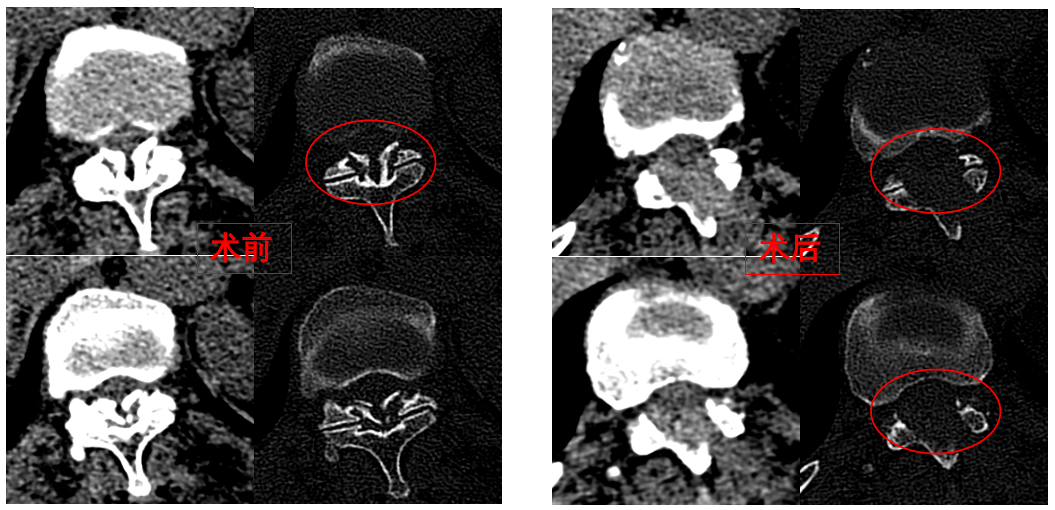

華西醫(yī)院成辦分院骨科副主任醫(yī)師張斌接診后,憑借豐富的脊柱治療經(jīng)驗(yàn),立即安排卓瑪阿媽做了系列精密檢查,檢查結(jié)果顯示,阿媽胸椎11/12節(jié)段黃韌帶嚴(yán)重骨化,導(dǎo)致椎管顯著狹窄,脊髓受壓,確診為嚴(yán)重的“胸椎黃韌帶骨化癥”,如果不及時(shí)手術(shù)最終可能面臨癱瘓的風(fēng)險(xiǎn)。

手術(shù)歷時(shí)一個(gè)半小時(shí),骨科脊柱微創(chuàng)團(tuán)隊(duì)成功完整切除了壓迫脊髓的骨化黃韌帶,徹底解除了卓瑪阿媽的脊髓壓迫。手術(shù)過(guò)程順利,手術(shù)切口僅1厘米。

圖為卓瑪阿媽術(shù)前、術(shù)后胸椎CT照片對(duì)比。